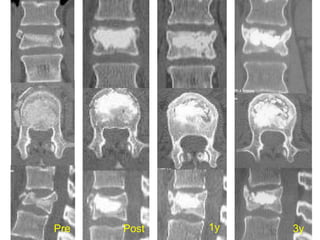

Pre Post 1y 3y

Kyphoplasty

It is important to fill the anterior 2/3–3/4

of the vertebral body

Cement should reach or cross the midline to

reinforce both halves of the vertebra (white